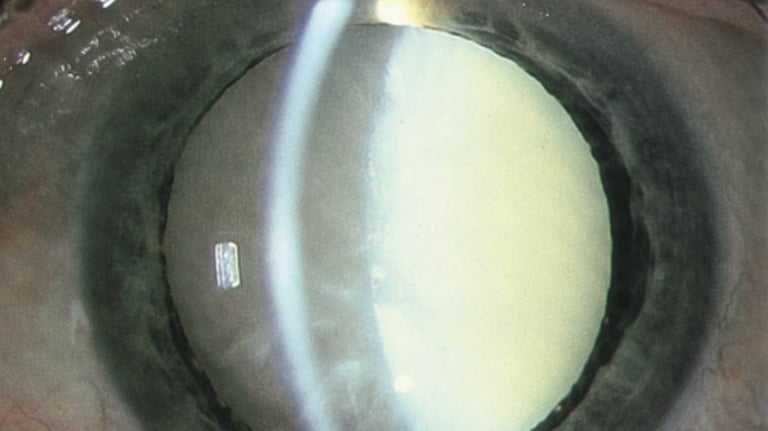

Doenças Oftalmológicas

Nesta seção, explicamos as doenças oculares mais prevalentes de forma clara e acessível. Nosso objetivo é ajudar você a entender as causas, sintomas e tratamentos de condições como catarata, glaucoma, degeneração macular e outras. Com informações simples e diretas, queremos que você se sinta informado e confiante para cuidar da sua saúde ocular. Caso tenha dúvidas, nossa equipe está à disposição para ajudar.